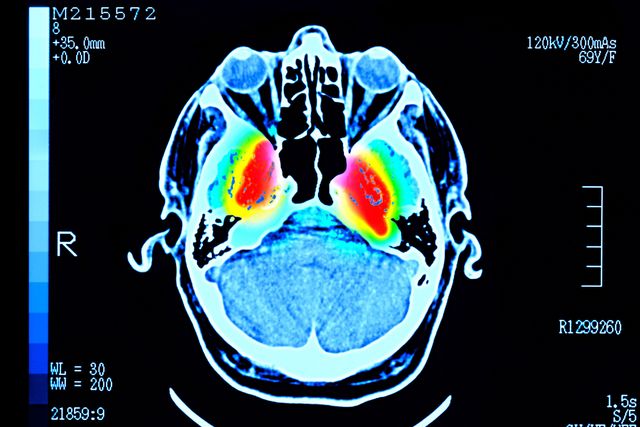

인간의 뇌를 스캔한 이미지. 중심에 붉은색, 노란색 등으로 표시되어 있다

Getty Images

연구진은 이번 연구 결과가 생애 주기에 따라 정신질환 혹은 치매 위험이 달라지는 이유를 이해하는 데 도움이 될 수 있다고 말한다